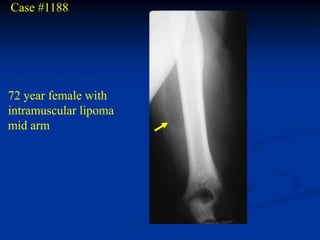

Case #1188

72 year female with

intramuscular lipoma

mid arm

Case #1188 72 yearfemale with intramuscular lipoma mid arm